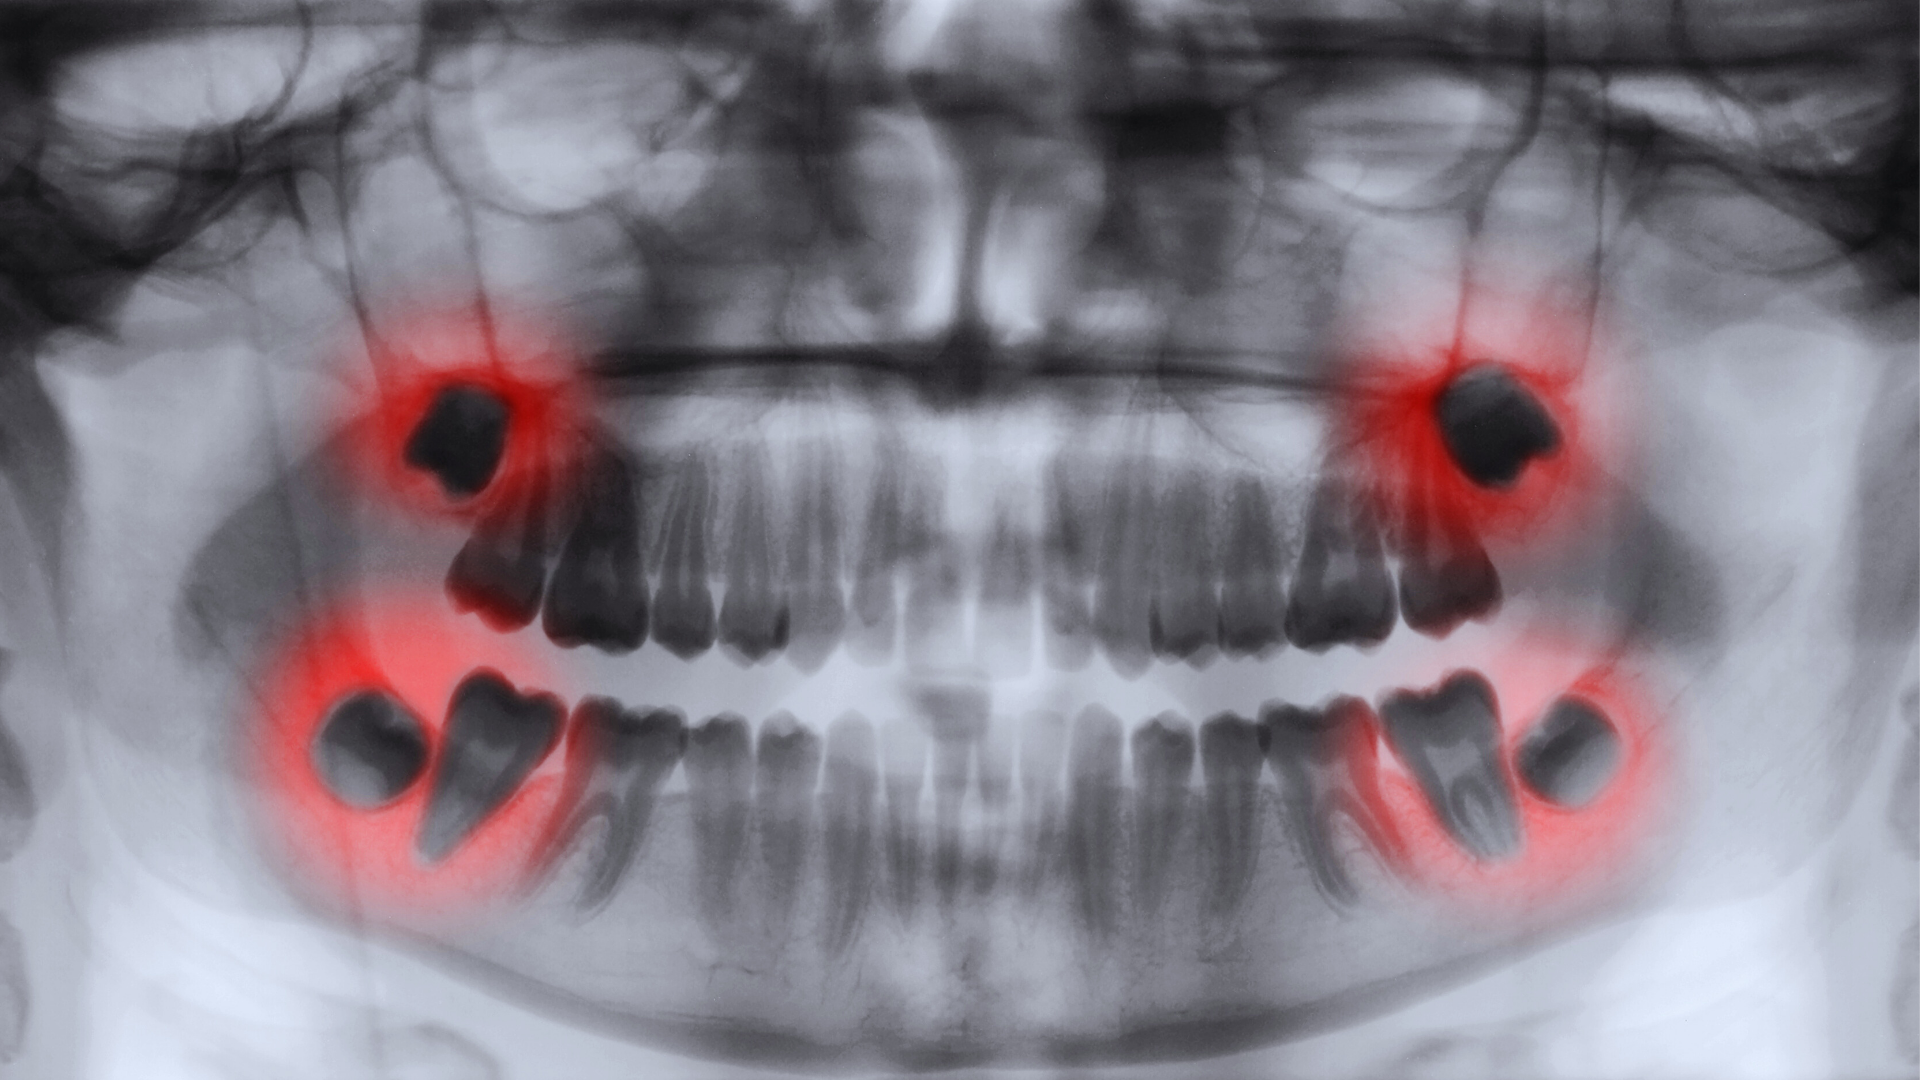

Cirugía de terceros molares

La cirugía de terceros molares, o “muelas del juicio”, es la extracción de estas piezas dentales debido a la falta de espacio, su mala posición o para evitar complicaciones futuras como infecciones, caries o quistes. El procedimiento se realiza con anestesia local, o con sedación. En nuestra clínica utilizamos instrumentación rotatoria para remover el hueso y tejido que los recubre, seguido de suturas.